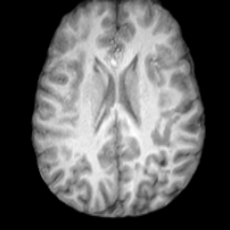

Figure 4: Qualitative results of USB on generation tasks. (a) unconditional generation, illustrating USB’s capability to generate lesion masks with diverse locations and complex shapes, together with their corresponding pathological brain images; (b) conditional generation, showing USB’s ability to generate unlimited pathological brain images conditioned on varying lesion masks.

Conditional Generation. Fig. 4 (b) shows conditional generation results given a lesion mask. Conditioned on a single lesion mask, USB can generate an unlimited brain image samples that embed the specified lesion, producing diverse anatomical appearances while maintaining faithful pathological localization. As illustrated by the samples along each row, the generated pathological images exhibit variations in intensity, texture, and local tissue response.

In Tab. 1, we present the first quantitative benchmark evaluation of both generation tasks. For the unconditional generation task, we generated 256 paired lesion–brain samples for each lesion type (stroke and WMH). For the conditional generation task, we used masks from the ATLAS and ISLES test sets as stroke lesions, and masks from the ADNI test set as WMH lesions. Notably, for each lesion type, the unconditional generation achieved superior quantitative performance, highlighting that the paired diffusion mechanism effectively generates coherent lesion-brain pairs through joint modeling between USBbrain and USBlesion. Additional generation results are provided in Suppl. A.